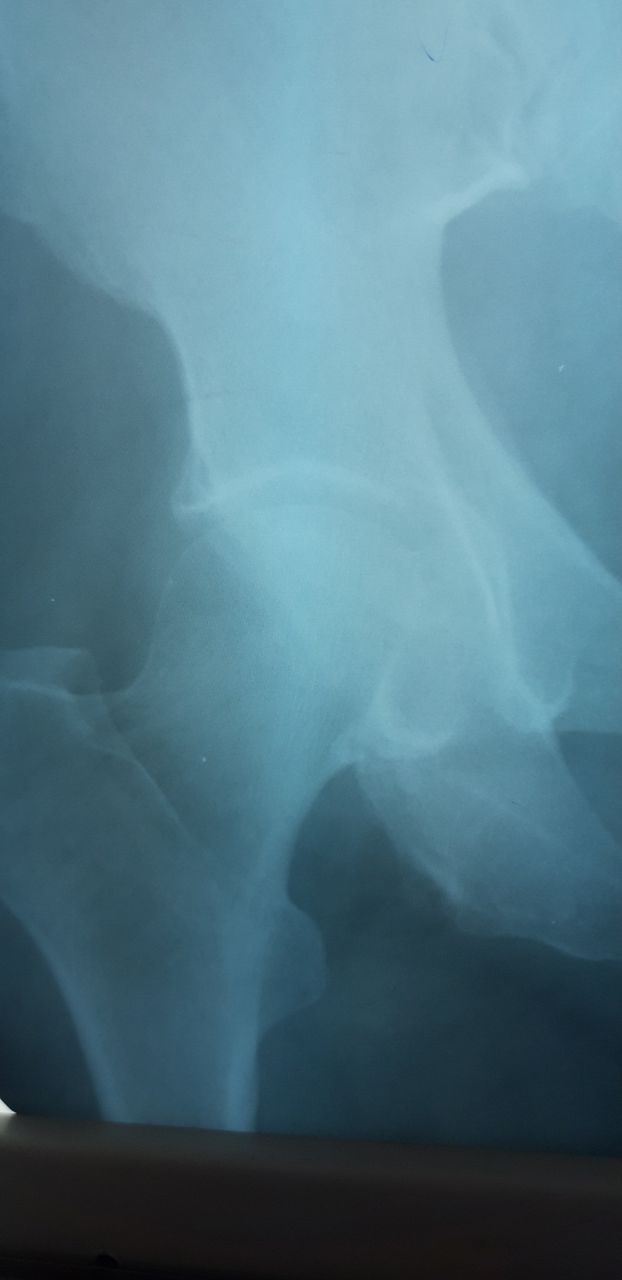

Подскажите,это перелом справа?женщина 1949г.р

Перелом седалищной кости справа?

Боковой сделали. Подскажите как описать

В таких ситуациях очень учёные травматологи говорят что это старый перелом

В таких ситуациях очень учёные травматологи говорят что это старый перелом